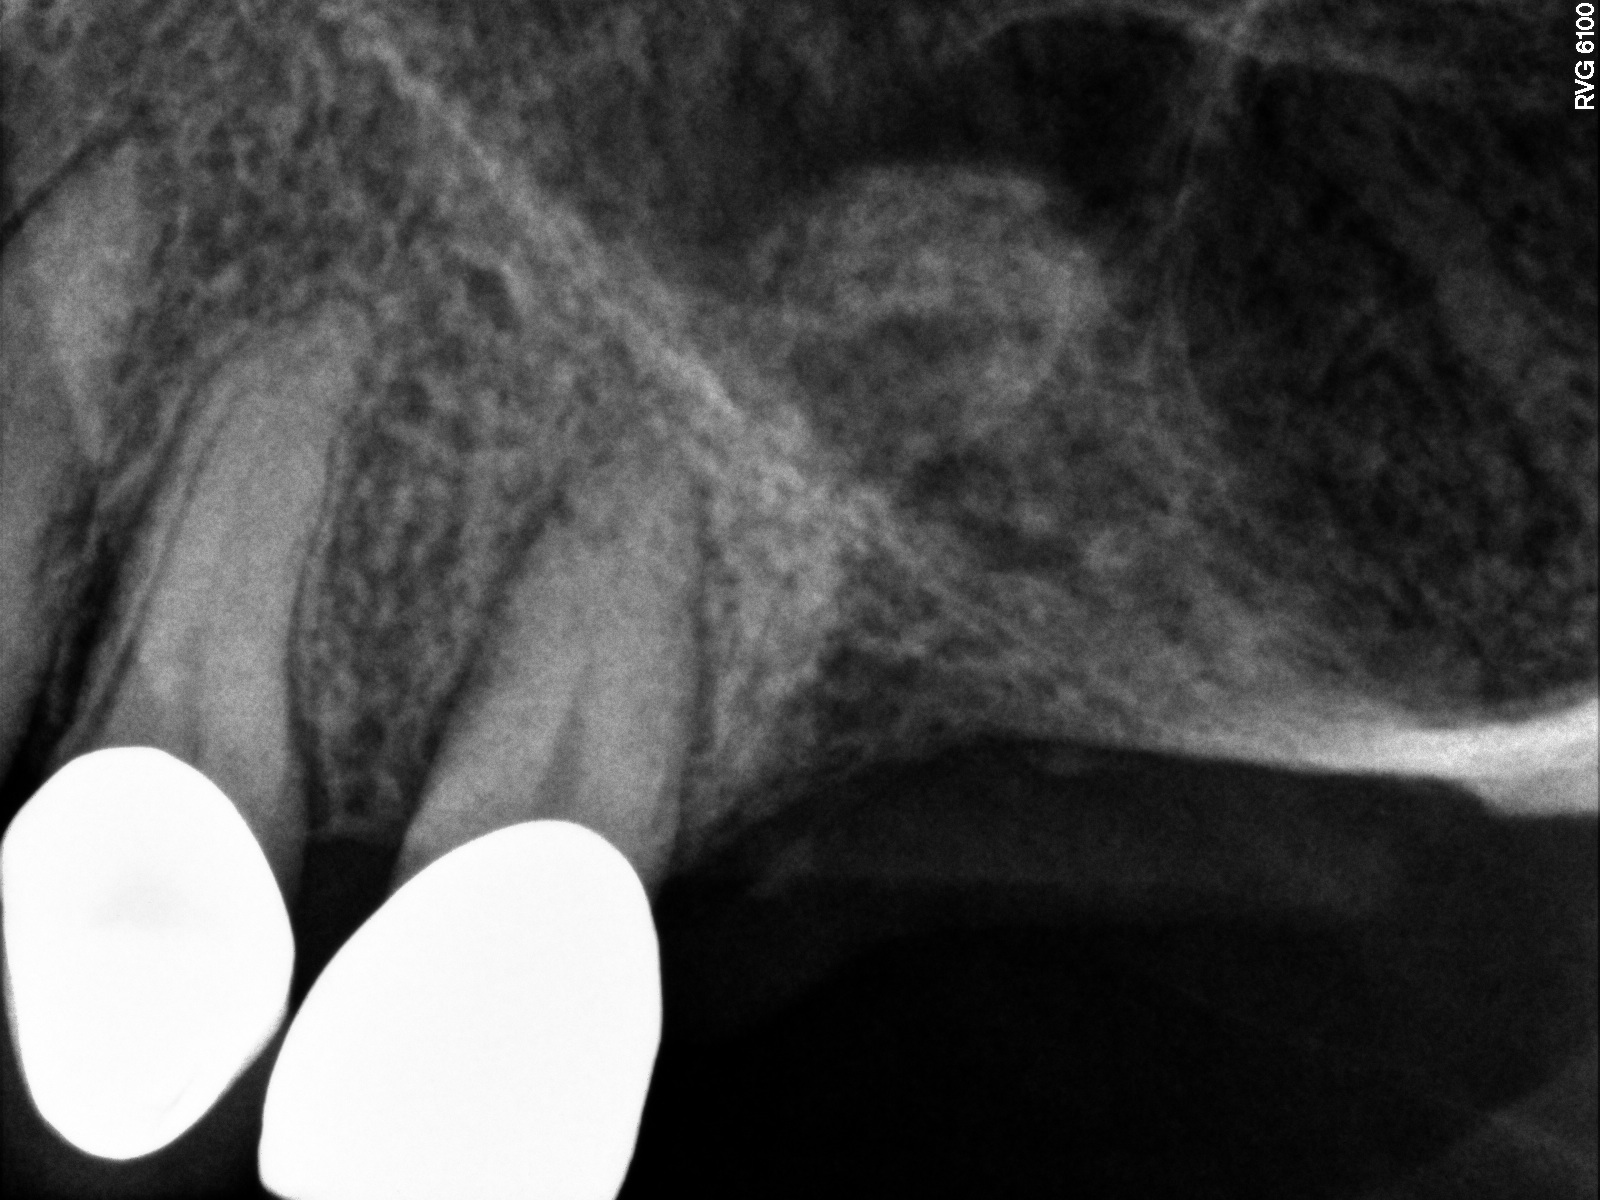

Case 1. Preoperative radiograph showing a ridge height of about 2 mm to 3 mm in the No. 14 position.

Fig. 13